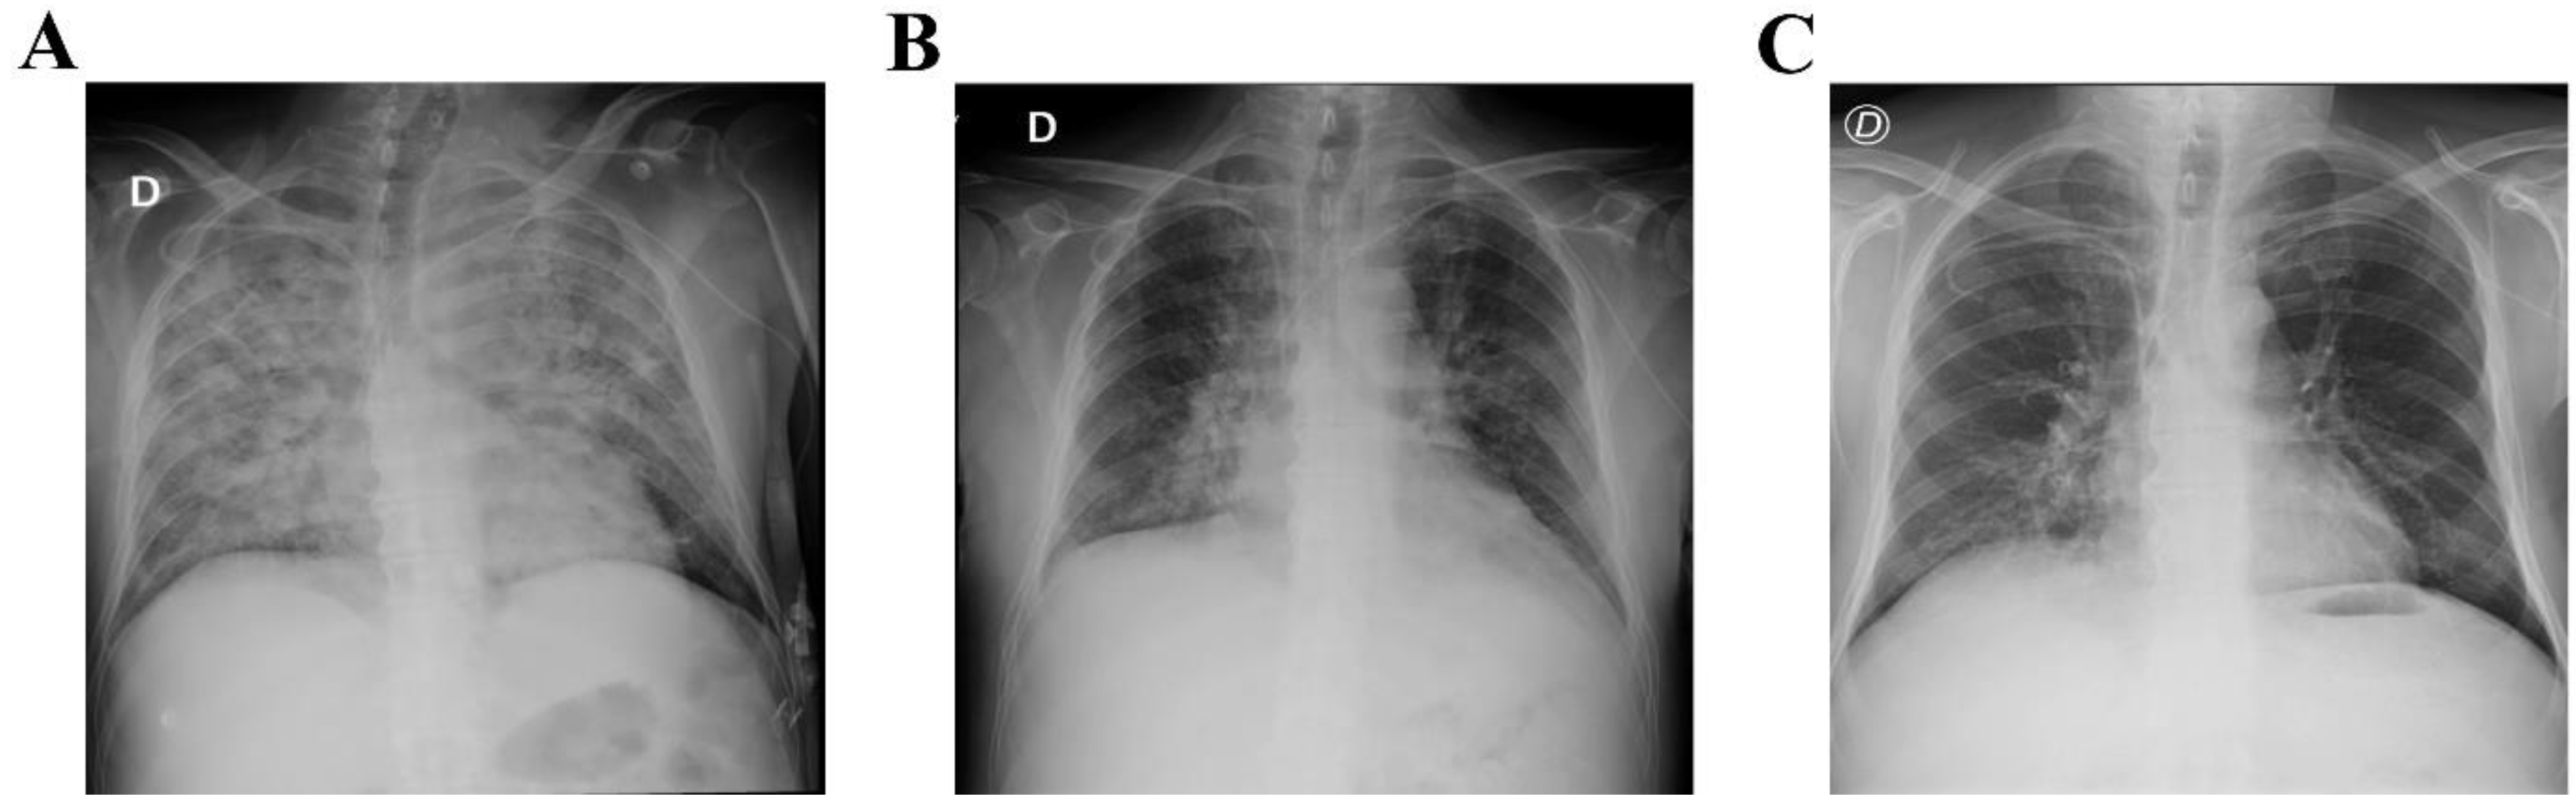

Figure 1.

Chest X-ray before and after intravenous immunoglobulin substitution (IVIG). (A) Chest X-ray with signs of bilateral pneumonia before starting IVIG treatment. Chest X-ray after 3 days (B) and 5 days (C) of IVIG replacement showing improvement of the pneumonia.

A 44-year-old Colombian man was admitted in a third level Clinic in Cali, Colombia at the end of February 2021 (rainy season). The patient had been diagnosed with acute lymphoblastic leukemia (ALL) two years previously, with history of two relapses. He referred five days of fever with no apparent cause. He had been treated with blinatumomab as a bridging therapy to stem cell transplant (SCT) and had finished the first month of treatment with blinatumomab ten days previously. Physical examination showed generalized paleness with normal vitals. At the time of admission, the patient was conscious and did not present urinary or respiratory symptoms. Pancytopenia was observed (Table 1). Blood transfusion of irradiated red blood cells and platelets was indicated; however, the pancytopenia did not improve, and other blood transfusions were required. Blood cultures were obtained and treatment with meropenem was initiated due to febrile neutropenia. Twenty-four hours after admission, the patient began to present respiratory symptoms, oxygen desaturation up to 60%, occasional cough, tachycardia, and hypotension. Treatment with vancomycin, amikacin and fluconazole was started. Chest X-ray showed increase in cotton wool opacities with commitment of all quadrants associated with bilateral broncho-pneumonic infiltrate in the consolidation process (Figure 1). Treatment for influenza virus (oseltamivir), Pneumocystis jirovecii (trimethoprim/sulfamethoxazole) and atypical bacterial infection (iv clarithromycin) was indicated, and COVID-19 was suspected. PCR and antigen detection in nasopharyngeal aspirate for SARS-CoV-2 were negative. Multiplex molecular detection of microorganisms (FilmArray, Biofire, USA) was requested. The patient continued presenting a rapid deterioration of his general condition with worsening of the respiratory pattern, desaturation, and severe hypoxemia, requiring non-invasive mechanical ventilation (the patient refused intubation). A CT scan of the lungs revealed severe bilateral bronchopneumonia, inflammatory hilar ganglia, and minor pleural effusion (Figure 2). Microbiological tests for bacteria, fungi, and mycobacteria were negative, but FilmArray was positive for coronavirus HCoV-NL63.There was no obvious contact with other people infected with HCoV-NL63. There is no specific treatment for this virus infection, thus supportive treatment was continued. Owing to the treatment with blinatumomab, secondary antibody deficiency was suspected, and humoral immune response was evaluated. Protein electrophoresis and serum immunoglobulins(IgG, IgA and IgM) levels revealed severe hypogammaglobulinemia (Table 1). Replacement therapy with intravenous immunoglobulins (IVIG) at a dose of 400 mg/kg (every 28 days) was indicated. Interestingly, the patient improved oxygenation diminishing supplementary oxygen requirement after only 24 hours from IVIG administration. The clinical evolution was adequate and the respiratory syndrome improved after 72 hours from IVIG administration (second molecular testing was not available). Treatment with blinatumomab was restarted. After the second dose of IVIG, his general health condition was good, and the patient was discharged. Currently the patient shows a good engraftment after 6 months from stem cell transplant with matched sibling donor, but he is still requiring IVIG due to hypogammaglobulinemia persistence (data not shown).